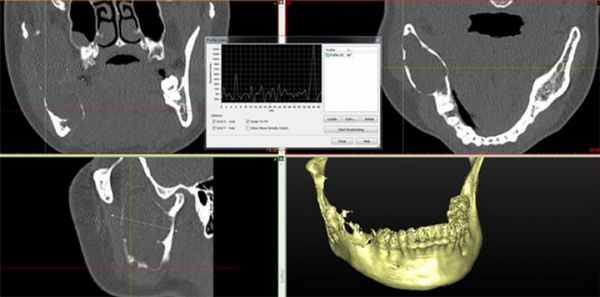

Клинический случай №3

Пациент муж., 50 лет, в анамнезе операция удаления амелобластомы в пределах видимо здоровых тканей. Обратился с жалобами на повторное развитие опухолеподобного образования (Рис. 4).

Рис. 4. КТ свидетельствует о рецидиве кистозной формы амелобластомы.

Поражено тело нижней челюсти больше справа, определяется «вздутие» и неравномерное истончение передней пластины тела челюстной кости, обширный участок деструкции с четкими, полицикличными контурами, неправильной овальной формы, размерами 4,5 х 3,5 х 3,0 см. Кортикальный слой передней поверхности челюсти значительно истончен, местами не определяется, периостальная реакция отсутствует. В патологически измененном участке видны перегородки и известковые включения. Правое ментальное отверстие и дистальный отдел канала правого нижнеальвеолярного нерва не определяется.